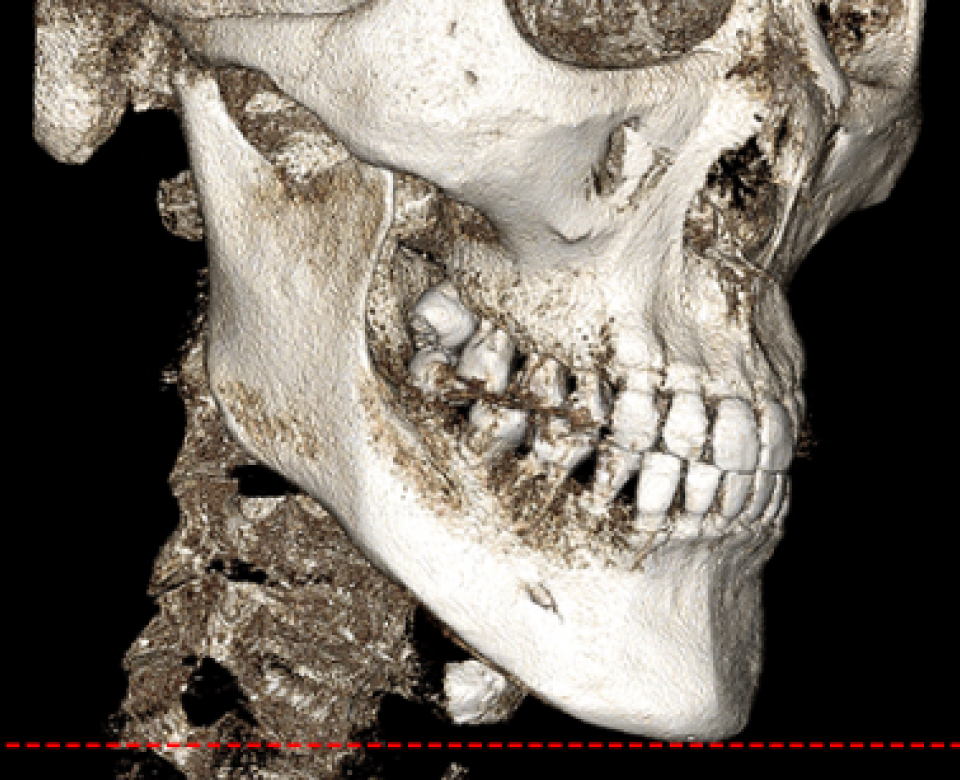

수술 전 3D-CT를 통해 신경의 위치를

1mm까지 분석하고,

원장님이 직접 수술 경로를 디자인하여

신경 손상을 원천 차단합니다

* 수술전 원장님이 직접 디자인한 사진입니다